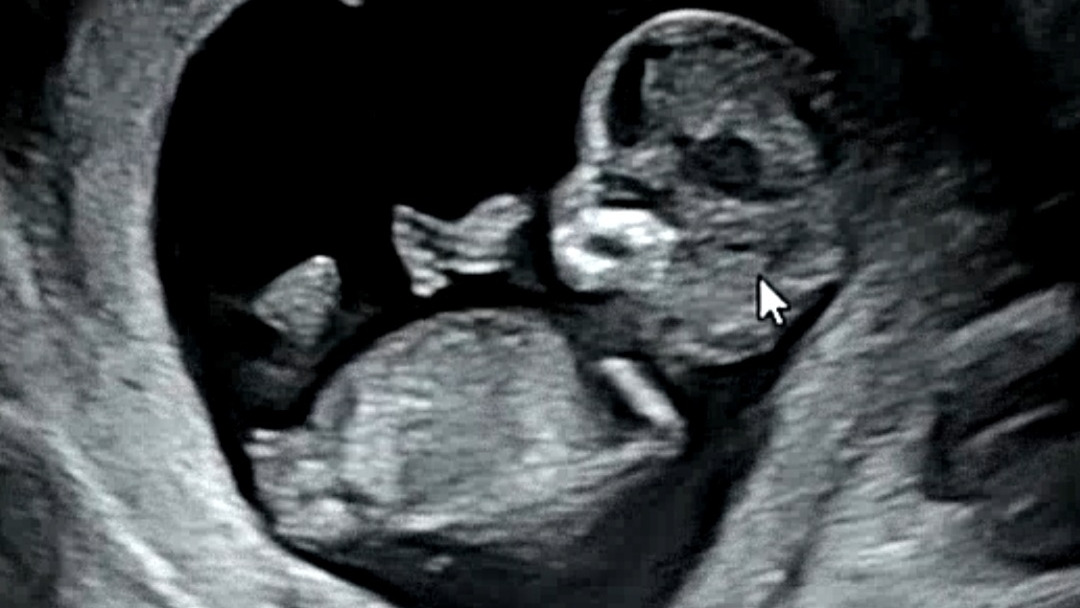

나에게 새로운 생명이 찾아왔다.

태명 '덕 있고 순한 아이', 덕순이.

덕순이를 처음 알게 된 순간부터

심심했던 내 인생에 새로운 목표가 생겼다.